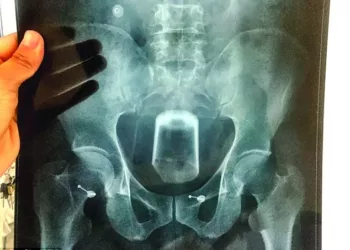

Un bărbat a fost transportat la un spital din China în urma unei urgențe medicale mai ciudate. Bărbatul avea un...